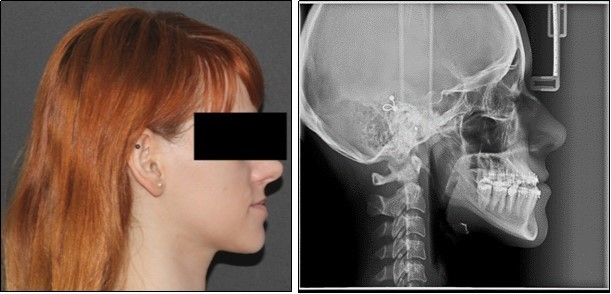

Orthodontic examination digital photographs were taken before the patient underwent the initial cinical examination. Frontal esthetic analysis revealed a long face, an increased third floor of the face and an asymmetry due to mandibular deviation to the left. Lateral view analysis disclosed a concave profile, with a deficient nasomaxillary area and proeminent chin. The lower lip was protruded, the upper lip was retruded and the mentolabial anlge was reduced. (Figure 1)

The pre-surgical orthodontic preparation successfully met the following objectives: levelling and aligning, flattening of curbe of Spee, proclination of the lower incisors and elimination of dental compensations. Before surgery, the patient had a normal position of the lower incisors, with IMPA 88 degrees. (Figure 4) Before surgery, a slight anterior open bite and an anterior crossbite could be observed, due to the elimination of dental compensations. Crimpable hooks were placed between each tooth on the 0.019x0.025 SS archwires, to allow placement of intermaxillary elastics after surgery. (Figure 5).

Figure 4.Pre-surgical extraoral photographs, after orthodontic preparation and preoperative lateral cephalometric radiograph

Post-surgical orthodontic treatment was started 4 weeks after the surgery. Wearing of bilateral box elastics was recommended in order to improve interdigitation. (Figure 6) The orthodontic treatment was finished on 0.019x0.025 SS archwires. Post-surgery cephalometric analysis revealed an increase in SNA value by 4 degrees (SNA 82 degrees) and a decrease in SNB value also by 4 degrees (SNB 79 degrees). The patient was now in a skeletal class I, with ANB 3 degrees. An examination of the soft tissue on the radiograph reveales a better relation between the upper and lower lip. (Figure 7).